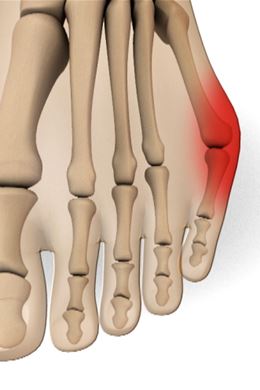

Een bunionette is een pijnlijk uitstekende knobbel net voor de kleine teen.

Die bunionette ontstaat meestal door een lichte scheefstand van het vijfde middenvoetsbeentje en overdruk van te smal schoeisel.